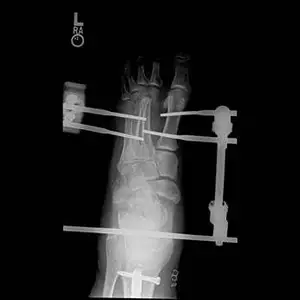

In the x-rays below there are fractures seen in the midtarsal bones that can occur with a high impact twisting injury where the foot is caught in something like the stirrup of a horse saddle or from direct high impact traums to the middle of the foot. The fractures can be seen from a view at the top of the foot (left) and side of the foot (right). This injury requires open reduction with internal fixation in order to re-align the fractured bones and prevent disability (Bottom left).

These are pics of the external fixator on to hold temporary reduction prior to internal fixation